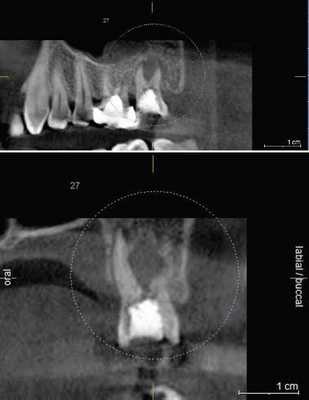

4. Резорбция корня

Резорбция корня это утрата твердых тканей зуба в результате активности остеокластов. Это может происходить в рамках физиологического или патологического процесса. Корневая резорбция может быть классифицирована на внешнюю и внутреннюю, в зависимости от локализации процесса относительно поверхности корня. Первые данные о внутренней резорбции получены в 1830. В сравнении с внешней резорбцией внутренняя является весьма редким процессом, этиология которого до конца не изучена. Точность КЛКТ при определении дефектов поверхности хоть и является более высокой по сравнению со стандартной техникой, но, все же, не идеальна и повышается при повышении разрешения вокселей снимка. КЛКТ также показала свою состоятельность при оценке постортодонтической апикальной резорбции, в частности корней латеральных резцов верхней челюсти при импактных клыках.

На КЛКТ внешняя резорбция проявляется как неравномерная рентгенопрозрачность и интактный канал зуба, внутренняя же резорбция выглядит как четкий очаг без прослеживания корневого канала.

КЛКТ с успехом применяется для определения внутренней резорбции и дифференциации ее от внешней. Обычная рентгенография часто не может выявить верный объем распространения, локализации и источник резорбтивного процесса. КЛКТ помогает в определении с тактикой лечения, а также предлагает составить верный прогноз на основе активности и распространенности поражения. И лечение, и результат лечения таким образом становятся более предсказуемыми.